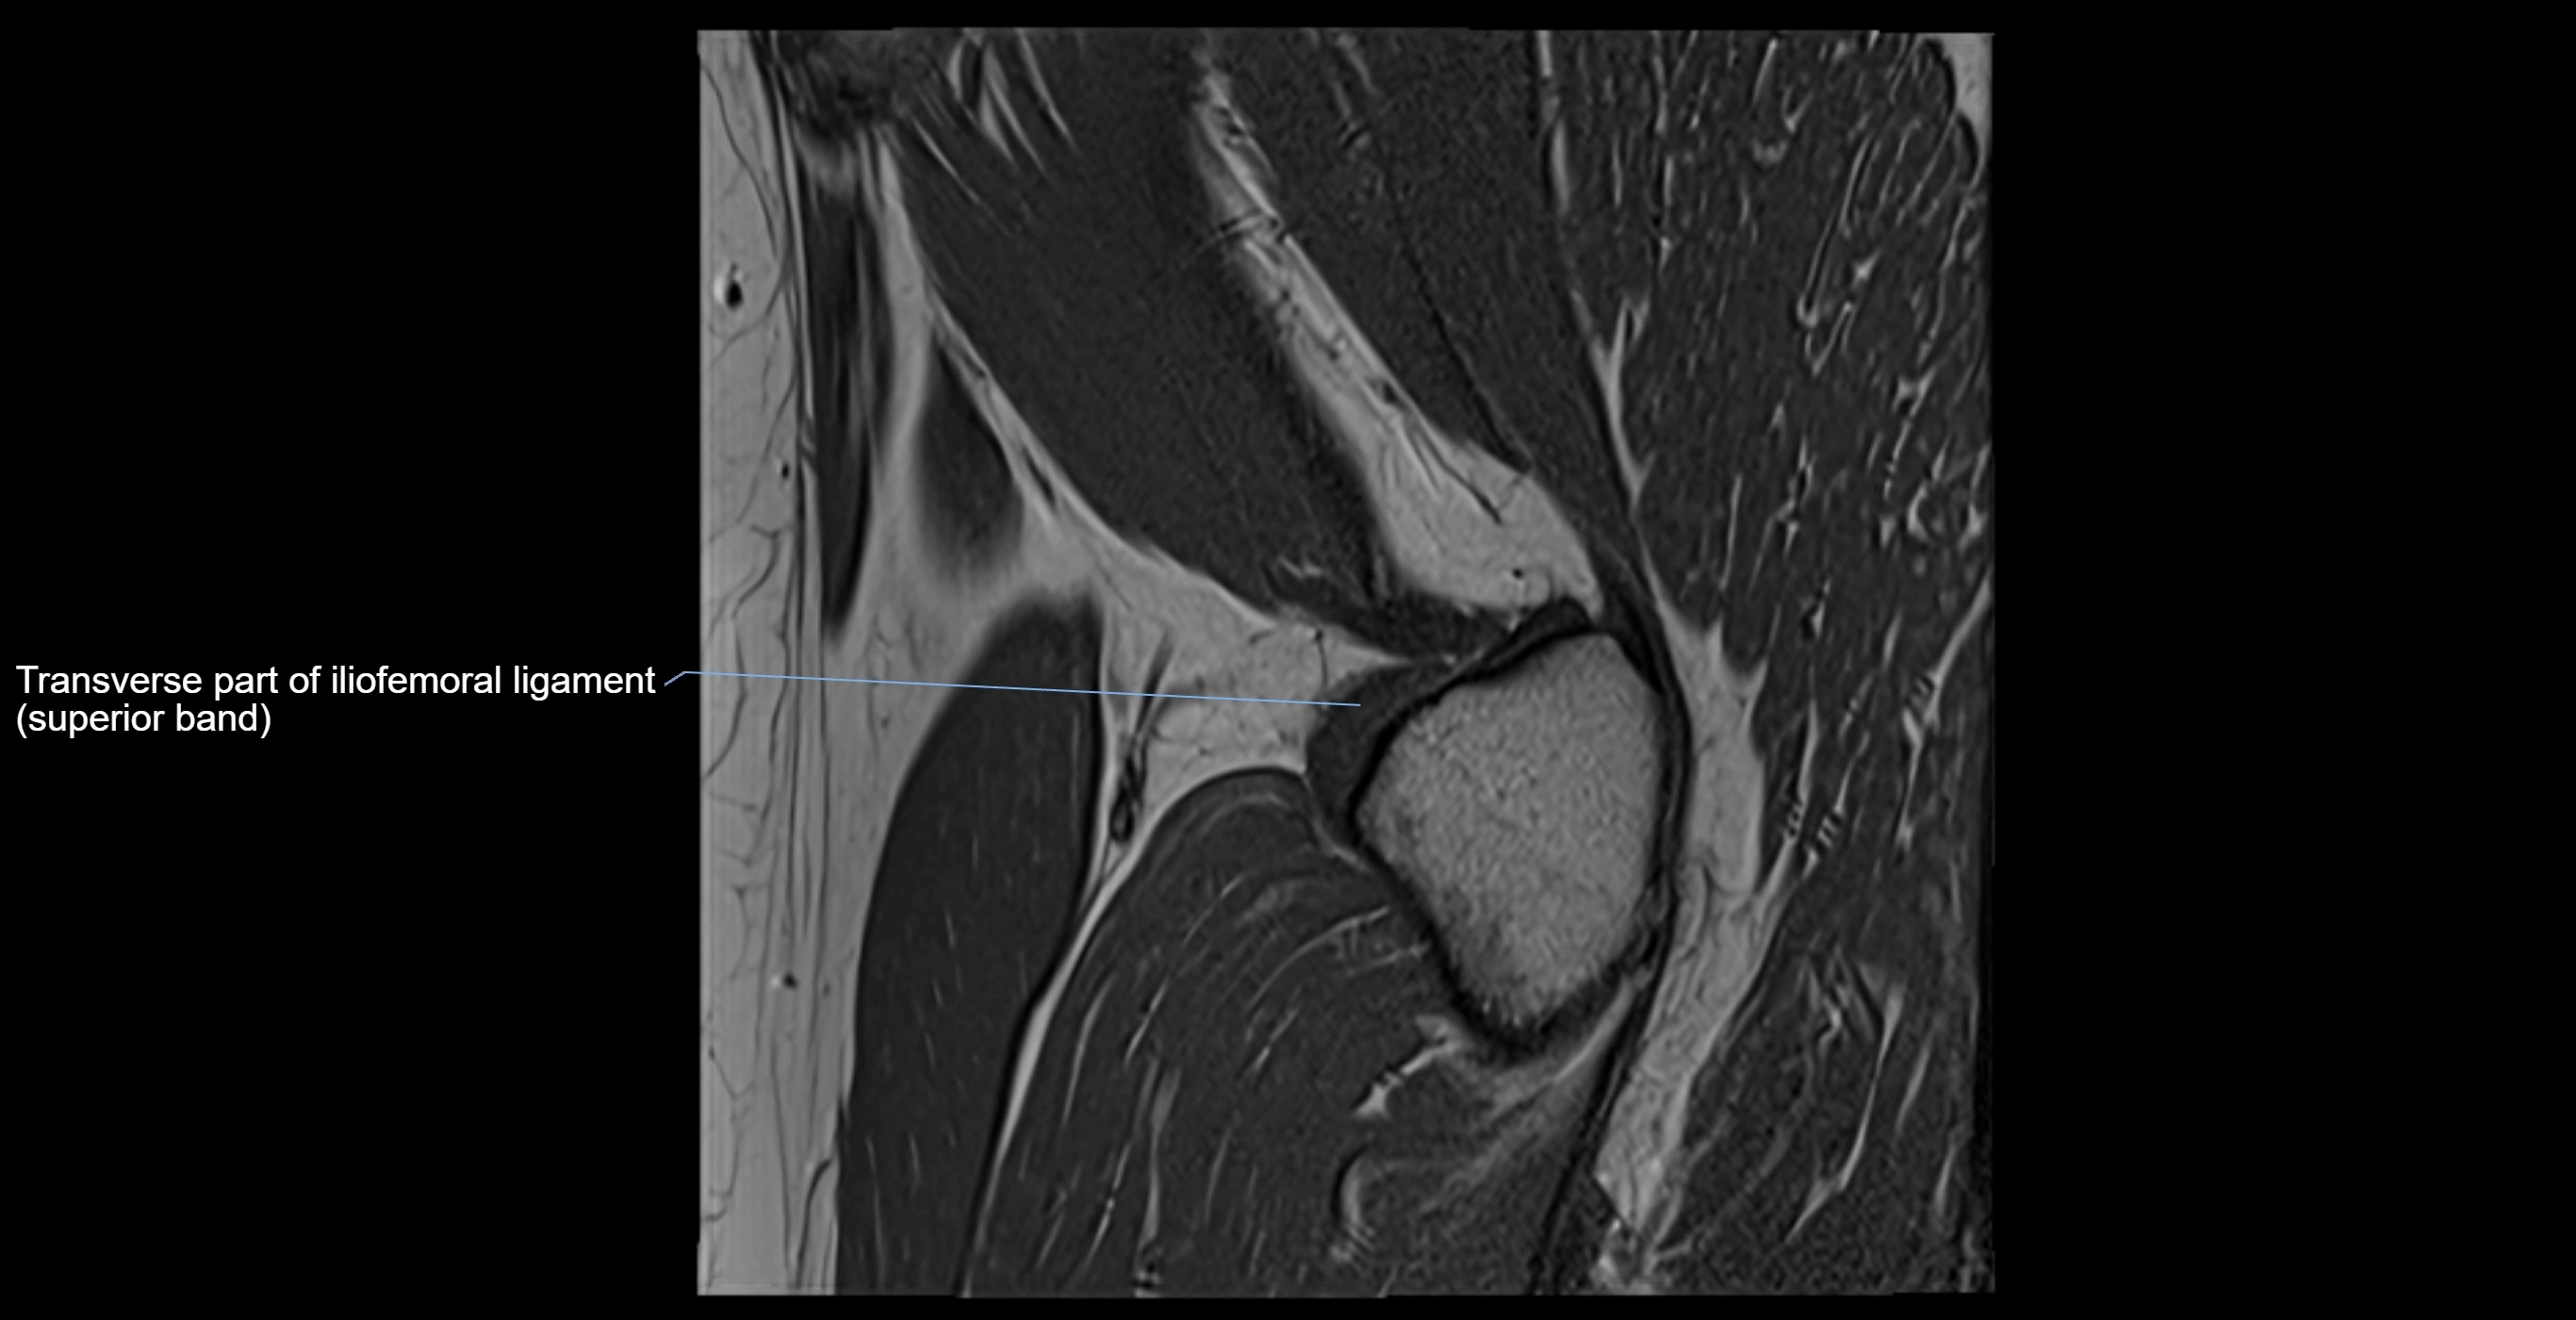

Acetabular labrum

The acetabular labrum is a fibrocartilaginous ring that surrounds the rim of the acetabulum in the hip joint. It deepens the hip socket, increases joint stability, and maintains a suction seal that preserves negative intra-articular pressure. Structurally, the labrum transitions from hyaline cartilage of the acetabulum to dense fibrocartilage at its free edge.

MRI Appearance

T1-weighted images:

• Labrum: low signal intensity (dark)

• Surrounded by intermediate signal joint fluid (bright on arthrogram)

• Tears: linear or focal areas of intermediate-to-high signal interrupting labral continuity

T2-weighted images:

• Joint fluid: bright, making labral tears visible as fluid extending into or around labrum